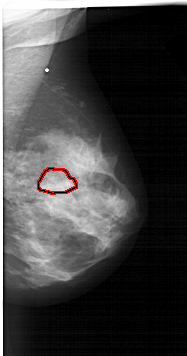

A_1566_1.RIGHT_CC

RIGHT_CC LINES 5866 PIXELS_PER_LINE 3151 BITS_PER_PIXEL 12 RESOLUTION 43.5 OVERLAY

FILE: A_1566_1.RIGHT_CC.OVERLAY

TOTAL_ABNORMALITIES 1

ABNORMALITY 1

LESION_TYPE MASS SHAPE LOBULATED MARGINS OBSCURED

ASSESSMENT 4

SUBTLETY 3

PATHOLOGY BENIGN

TOTAL_OUTLINES 1

BOUNDARY